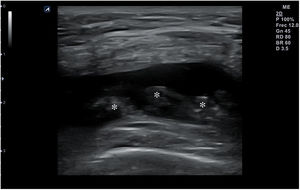

| GRADO 0: Ecografía negativa a pesar de clínica sugestiva Grado 1: Área sutil mal definida hiperecoica o hipoecoica sin defecto fibrilar objetivado o inflamación de la aponeurosis (fig. 3). Corresponde a una elongación con menos del 5% del músculo involucrado. El dolor puede ser intenso pero muy inespecífico Grado 2: Discontinuidad parcial de las fibras (fig. 4). Afecta entre el 5 y 50% del volumen muscular o del diámetro de la sección transversal. Defecto hipoecoico o anecoico dentro de las fibras musculares. Una suave presión con el transductor objetiva fragmentos desgarrados musculares que flotan en un fluido serohemático en «badajo de campana» Grado 3: Discontinuidad total de las fibras (fig. 5). Retracción completa del músculo. Lesiones clínicamente evidentes ya que el vientre retraído forma una masa muscular y un hachazo palpable en el músculo |

En la ecografía en el 50% de las lesiones grado 1 (fig. 3) se observará hiperecogenicidad en la lesión. En las de grado 2 (fig. 4) y 3 (fig. 5) se visualizarán regiones hipoecoicas indicativas de líquido adyacente a las fibras musculares. Se considera curación normal cuando hay una reducción en el tamaño o resolución de la región hiperecogénica, del hematoma o de la colección líquida. Si se demuestra tejido cicatricial durante el seguimiento es de importancia ya que, a mayor cicatrización, mayor riesgo de daño recurrente3.